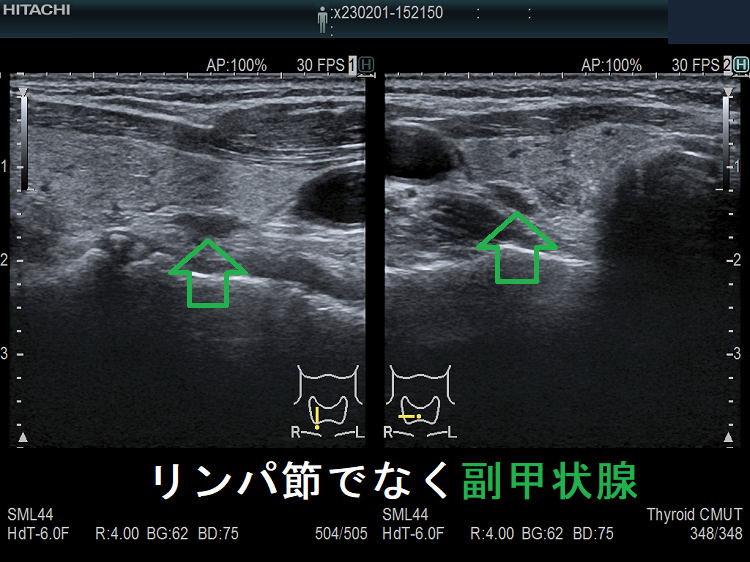

副甲状腺腺腫のように見えるも、実はただのリンパ節

副甲状腺腺腫との違いとして、リンパ節では

- 内部血流が無く

- リンパ門が存在します(ここだけ血流があります)

ケース③